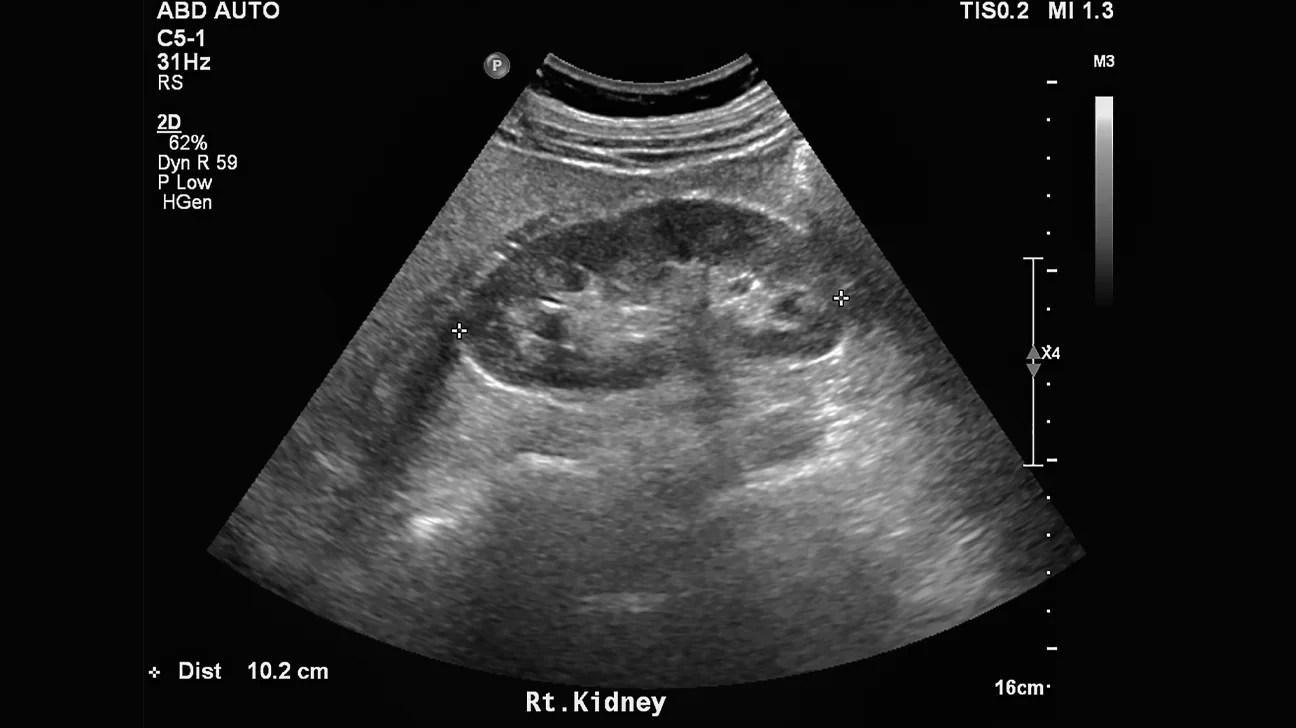

Le rein mesure environ 10 à 12 cm de hauteur.

Il présente trois zones caractéristiques :

• Cortex rénal : iso- à légèrement hypoéchogène par rapport au foie.

• Sinus rénal : très hyperéchogène (graisse + vaisseaux + voies excrétrices).

• Pyramides de Malpighi : hypoéchogènes, triangulaires, convergeant vers le sinus.

Le bassin rénal (pyélon) n’est normalement pas visible ou à peine suggéré par une fine ligne anéchogène.

La symétrie de taille et d’échogénicité entre les deux reins est essentielle.